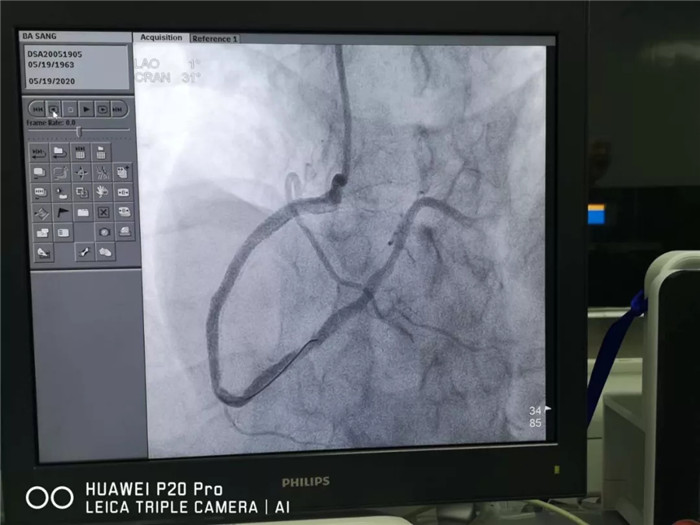

患者生命危急,与家属沟通同意介入(微创)手术;手术中,患者反复出现室颤、心脏停止跳动,均抢救成功,手术顺利结束,患者返回病房。两天后,患者又出现胸痛、胸闷症状,心电图检查,支持下壁严重缺血,再行冠状动脉血管造影复查,再次血运重建手术;目前,患者病情稳定,复查心电图、心脏B超、CT、化验正常,拟定出院。

术后影像